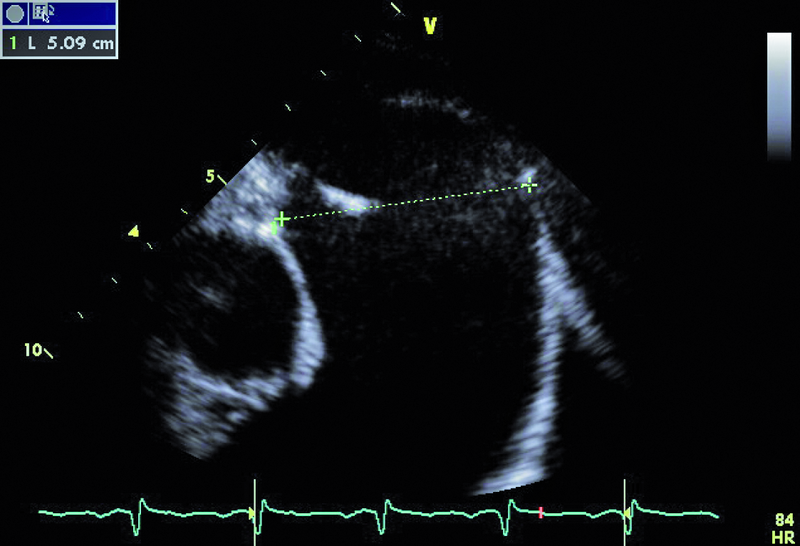

U chłopca, obecnie 16-letniego, wykonano w okresie noworodkowym zabieg operacyjny walwuloplastyki zastawki aortalnej z powodu wrodzonej stenozy. Uzyskano zmniejszenie gradientu maksymalnego z 50 do 16 mm Hg. W ciągu wielu lat obserwacji w ośrodku kardiologii dziecięcej gradienty przepływu przez zastawkę były niskie, a stan kliniczny pacjenta dobry. Sytuacja zmieniła się przed kilkoma miesiącami. Chłopiec został przyjęty do szpitala z powodu męczliwości, szybkiej częstości serca (do 90/min w rytmie zatokowym z pojedynczą ekstrasystolią komorową). Prawdopodobną przyczyną pogorszenia stanu zdrowia była przebyta wcześniej infekcja górnych dróg oddechowych. W badaniu przedmiotowym zwracał uwagę szmer holosystoliczny na koniuszku, promieniujący do pachy. W EKG rejestrowano cechy przerostu i przeciążenia mięśnia lewej komory. Wykonano cewnikowanie serca, stwierdzając nadciśnienie płucne ze średnim ciśnieniem w kapilarach płucnych 29 mm Hg. Pacjent był leczony intensywnie lekami moczopędnymi, beta-adrenolitykami i amiodaronem. Wobec braku poprawy skierowano go na oddział kardiologii dorosłych w celu rozważenia wskazań do leczenia operacyjnego. W badaniu echokardiograficznym zwracały uwagę wąskie strumienie niedomykalności zastawki aortalnej z czasem PHT wynoszącym 206 ms, istotnie powiększona jama lewego przedsionka z powierzchnią około 50 cm2, ciężkie nadciśnienie płucne z ciśnieniem skurczowym w jamie prawej komory 114 mm Hg!, rejestrowanym z małej fali zwrotnej trójdzielnej. Nie stwierdzono wady przeciekowej.

Chłopiec przebył w okresie noworodkowym zabieg walwuloplastyki aortalnej powikłany niedomykalnością zastawki (ryc. 1). Wada miała charakter przewlekły i spowodowała pojawienie się mechanizmów wyrównawczych. Jednym z nich jest zwiększenie objętości lewej komory i przyspieszenie rytmu serca. Frakcja wyrzutowa lewej komory jest zachowana (ryc. 2). Z pewnością infekcja górnych dróg oddechowych była czynnikiem inicjującym niekorzystny dla chorego przebieg zdarzeń. Ocena ciężkości niedomykalności aortalnej na podstawie parametrów ilościowych jest w tym przypadku trudna. Czas połowicznego spadku gradientu ciśnień PHT (aorta – lewa komora) oraz strumień fali zwrotnej w badaniu kolorowego doplera mogłyby wskazywać na umiarkowaną niedomykalność. Nie można jednak zapominać o możliwości zwiększenia ciśnienia rozkurczowego w jamie lewej komory, istotnie zmniejszającego gradient wsteczny i zakres fali zwrotnej. W przypadku dwustrumieniowej fali zwrotnej (jak w tym przypadku) talii cząstkowych niedomykalności nie sumuje się. Podobnie ograniczone zastosowanie w tym wypadku (ekscentryczne fale zwrotne) ma metoda ERO. Najprawdopodobniej wtórną do niedomykalności aortalnej wadą jest niedomykalność mitralna wynikająca z poszerzenia jamy lewej komory i poszerzenia pierścienia zastawki mitralnej. Niedomykalność mitralna także wydaje się co najwyżej umiarkowana (ryc. 3). Należy pamiętać, że i w tym wypadku szerokość strumienia fali zwrotnej zależy od wysokości ciśnienia w jamie przyjmującej, czyli w lewym przedsionku. Na podstawie przedstawionego materiału (ryc. 4-6) można stwierdzić, że nadciśnienie płucne u chłopca (postkapilarne) jest ciężkie, a ciśnienia uległy istotnemu zwiększeniu w porównaniu z wartościami stwierdzanymi wcześniej podczas cewnikowania serca (ciśnienie rozkurczowe płucne 54 mm Hg, średnie 74 mm Hg!). Warto zwrócić uwagę na profil spływu z żył płucnych. Zaznacza się w nim bardzo krótka faza odzwierciedlająca wyłącznie rozkurczowy napływ krwi do lewego przedsionka. Zwiększona objętość jamy przedsionka, wysokie ciśnienie krwi w niej panujące oraz ograniczona podatność ściany sprawiają, że w fazie skurczu komory nie rejestruje się napływu do jamy przedsionka. Podobnie bardzo wysokie ciśnienie w układzie żył płucnych sprawia, że nie obserwuje się przepływu wstecznego w związku z ciągle zachowanym skurczem przedsionka (rytm zatokowy). Chłopca zakwalifikowano do operacji dwuzastawkowej z powodu ciężkiej niedomykalności aortalnej i mitralnej. Zabieg implantacji zastawki biologicznej o średnicy 23 mm w ujście aortalne oraz pierścienia o średnicy 32 mm w ujście mitralne przyniósł dobry efekt.